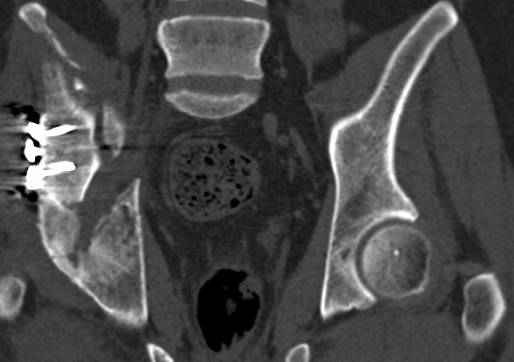

Re: перелом правой половины таза

высылаю дополнительно сканы.